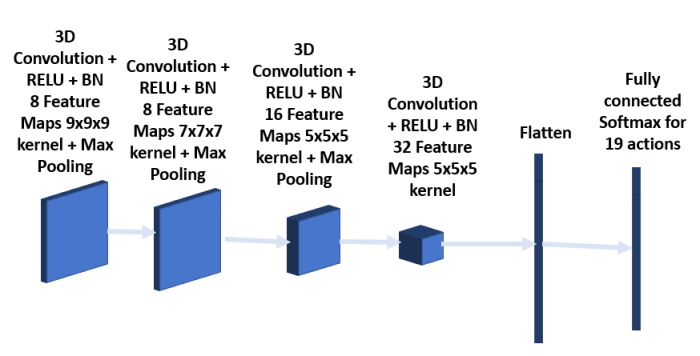

The policy network shown in Figure 5 is made up of three 3D convolution layers together with batch normalization and RELU activation. The kernel sizes of the first, second and third convolution layers are 7x7x7, 5x5x5 and 3x3x3 respectively. The network takes as input the data within the bounding box shrunk by half. The convolution layers are followed first by a fully connected layer and then by a softmax layer for 19 possible actions. The loss function used is mean square error.

To improve overall performance, two other CNN architectures were trained besides the one described above, and the predicted bounding boxes using all three models are provided to the next stage for analysis. The architecture of the second model consists of 6 convolution layers as shown in Figures 7 and 8 respectively. The first 2 layers have kernel size 7x7x7, followed by 2 convolution layers with kernel size 5x5x5 and the final 2 convolution layers having kernel size 3x3x3. Each convolution layer is followed by batch normalization. Max pooling is added after the second and fourth layer. The third model as shown in Figures 9 and 10 has a convolution layer with 9x9x9 kernel and a batch normalization preceding the architecture in the model shown in Figures 5 and 6.